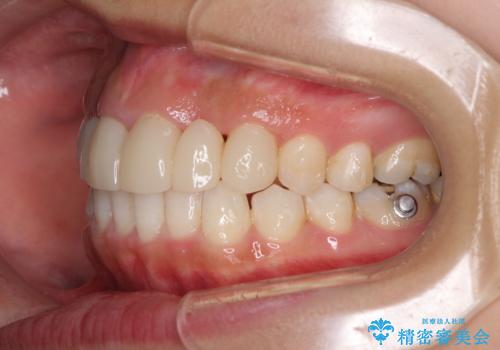

- 審美的ではない上の前歯とデコボコの下の前歯、歯茎が腫れている奥歯を気にして来院された患者様です。

根管治療の必要な歯がいくつかあるため、まずは根管治療を行い、その後インビザラインにて矯正治療を行うこととしました。

矯正治療後に前歯をセラミックブリッジに、奥の銀歯はセラミックインレーやPGAインレー(ゴールドインレー)にて補綴・修復治療を行うこととしました。